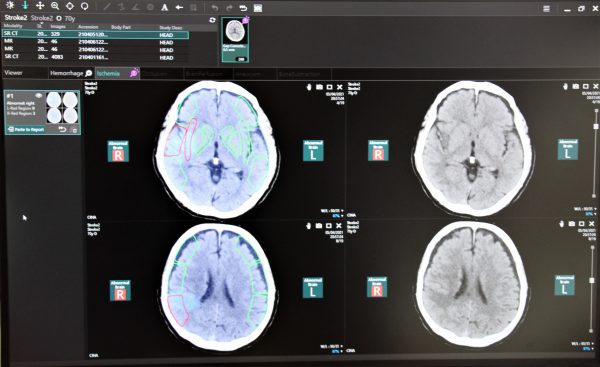

AIと医療スタッフが協調して画像診断をサポートする、読影診断支援ソリューション(Abierto / Reading Support Solution)。

脳血管疾患患者のQOLを高めるためSTROKEは、脳卒中疾患へのワークフロー改善を目的としたDeep Learning技術を内蔵した画像アプリケーションを搭載し、読影までのプロセスを自動化して速やかに検知情報を提供することで、治療方針策定を支援。また、新しい医療情報ソリューション「Abierto」シリーズでは、患者の治療や検査の情報を時間軸で統合し、医師別や診療シーン別に最適の情報を提供する。3D医用画像解析システムAZE Virtual Placeは、各種画像診断用途に対応した数多くの解析機能を備える。